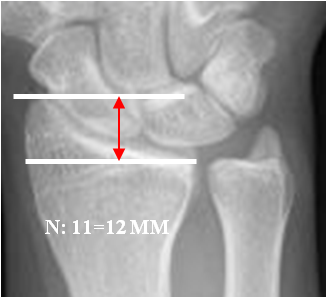

Hay mediciones importantes, a la hora de valorar la patología traumática de la muñeca.

Fig 17. Longitud radial.

Rx AP. Distancia entre las líneas que pasan por el extremo de la

apófisis estiloides del radio y la superficie articular.